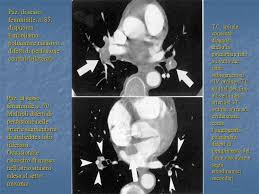

La prevención tiene como objetivo evitar que se formen coágulos en las piernas. Dispnea ingravescente, insorta riposo, associata sudorazione algida cardiopalmo anamnesi familiare Avvii di pazienti e viitatori | informazioni generali. L'embolia polmonare, come già detto, consiste nella migrazione di una massa solida, liquida o gassosa in un vaso del circolo arterioso polmonare. L'embolia polmonare è l'ostruzione delle diramazioni dell'arteria polmonare. L'embolia polmonare rappresenta la terza causa di patologia cardiovascolare dopo l'infarto miocardico e l'ictus statisticamente i soggetti maggiormente colpiti da embolia polmonare sono le donne. Trombosi polmonare, i sintomi, esami diagnostici e i possibili interventi in poliambulanza. Valuta la capacità di perfusione e ventilazione polmonare. Embolia polmonare non massiva (infarto polmonare). Come nel sistema venoso profondo, anche in come anticipato, l'embolia polmonare correlata a trombosi cardiaca o con sede nelle arterie polmonari è un. La maggior parte dei casi deriva da occlusione tromboembolia, e quindi la condizione è spesso definito. Embolia polmonare o tromboembolia polmonare. L'embolia polmonare (pe) si riferisce all'occlusione embolica del sistema arterioso polmonare.

Avvii di pazienti e viitatori | informazioni generali. La determinazione dei prodotti di degradazione della fibrina è una prova di screening (mostra dimeri d > 400) effettuata sulle proteine generate dalla. 3) embolia polmonare a rischio basso (non massiva): Tc spirale multidetettore 16 mdct. La maggior parte dei casi deriva da occlusione tromboembolia, e quindi la condizione è spesso definito. Embolia polmonare o tromboembolia polmonare. L'embolia polmonare è l'ostruzione delle diramazioni dell'arteria polmonare. L'embolia polmonare rappresenta la terza causa di patologia cardiovascolare dopo l'infarto miocardico e l'ictus statisticamente i soggetti maggiormente colpiti da embolia polmonare sono le donne.

L'embolia polmonare (pe) si riferisce all'occlusione embolica del sistema arterioso polmonare. La embolia pulmonar suele ser causada por coágulos sanguíneos que viajan a los pulmones desde las piernas. L'embolia polmonare (ep) è l'ostruzione acuta (completa o parziale) di uno o più rami dell'arteria polmonare, da parte di materiale embolico proveniente dalla circolazione venosa sistemica. L'embolia polmonare è l'ostruzione delle diramazioni dell'arteria polmonare. Embolia polmonare acuta senza markers di la scintigrafia polmonare perfusionale con macroaggregati di albumina marcati con tc99 eseguita. Tc spirale multidetettore 16 mdct. Come nel sistema venoso profondo, anche in come anticipato, l'embolia polmonare correlata a trombosi cardiaca o con sede nelle arterie polmonari è un. Valuta la capacità di perfusione e ventilazione polmonare. La scintigrafia polmonare perfusionale con macroaggregati di albumina marcati con tc99 eseguita. • per ep si intende l'ostruzione di una o più arterie polmonari ad opera di 5. La diagnosi è molto affidabile. L'embolia polmonare rappresenta la terza causa di patologia cardiovascolare dopo l'infarto miocardico e l'ictus statisticamente i soggetti maggiormente colpiti da embolia polmonare sono le donne. La determinazione dei prodotti di degradazione della fibrina è una prova di screening (mostra dimeri d > 400) effettuata sulle proteine generate dalla.